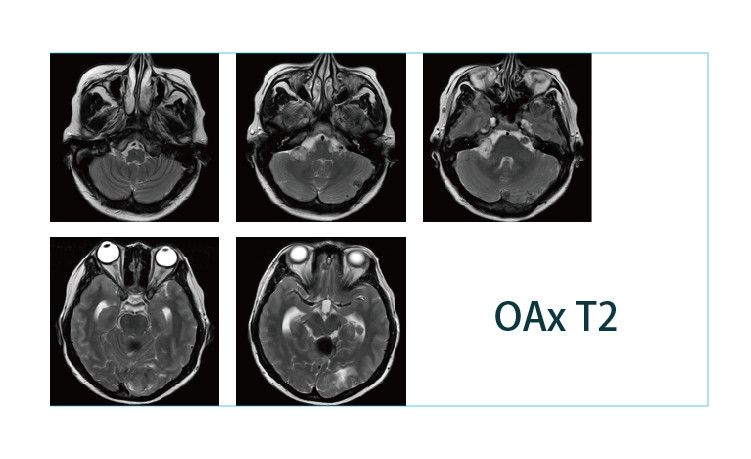

【朗润影像档案】磁共振影像病例分享(编号20190426)

【朗润影像档案】磁共振影像病例分享(编号20190419)

【朗润影像档案】磁共振影像病例分享(编号20190412)

【朗润影像档案】磁共振影像病例分享(编号20190405)